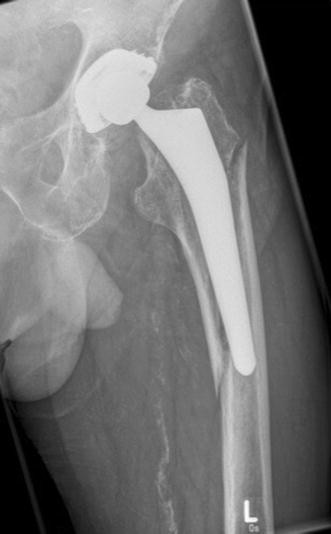

Fracture after total hip replacement. I had to have a week�s complete bedrest before the second operation, and have been told to use crutches for 6 weeks (full weight bearing). Broken femurs are treated with surgery and physical therapy. The surgical procedure used to repair a broken hip may vary depending on a number of factors. If the femoral neck fracture is not at all displaced (out of position), then a repair of the break may be considered. A periprosthetic hip fracture is a broken bone that occurs around the implants of a total hip replacement.

Hip fracture after total hip replacement may involve a fracture of the bone around the implant or of the bone directly surrounding the implant.

In general, fractures of the very top of the thigh bone, called the femoral neck, are treated with replacement. Broken femurs are treated with surgery and physical therapy. Sometimes screws are attached to a metal plate that runs down the thighbone (femur). Sometimes the femur fractures before, during or after hip replacement surgery. Although a fracture may occur during a hip replacement procedure, the majority of periprosthetic fractures occur after a patient has spent years functioning well with a hip replacement.

The femur (thighbone) can be split or cracked during hip replacement surgery due to poor use of instruments during bone preparation or unexpectedly soft bone. The healing process, however, requires immobilizing the joint through complete bed rest, which often takes three to four months. Femur fracture repair — discharge. Although a fracture may occur during a hip replacement procedure, the majority of periprosthetic fractures occur after a patient has spent years functioning well with a hip replacement. Metal screws are inserted into the bone to hold it together while the fracture heals.